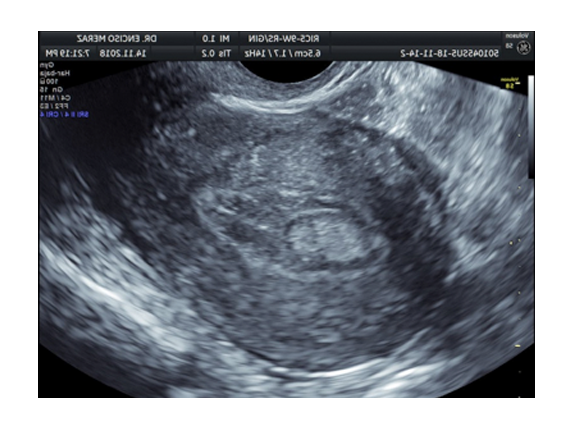

ULTRASONIDO VAGINAL O PÉLVICO

Efectuado para descartar alteraciones en utero u ovarios o bien en gestaciones menores 8 semanas a través del eco via vaginal. Tambien permite valorar la Longitud cervical en gestaciones con riesgo de prematurez, como aquellas madres que tuvieron contracciones, sangrados o nacimientos prematuros.